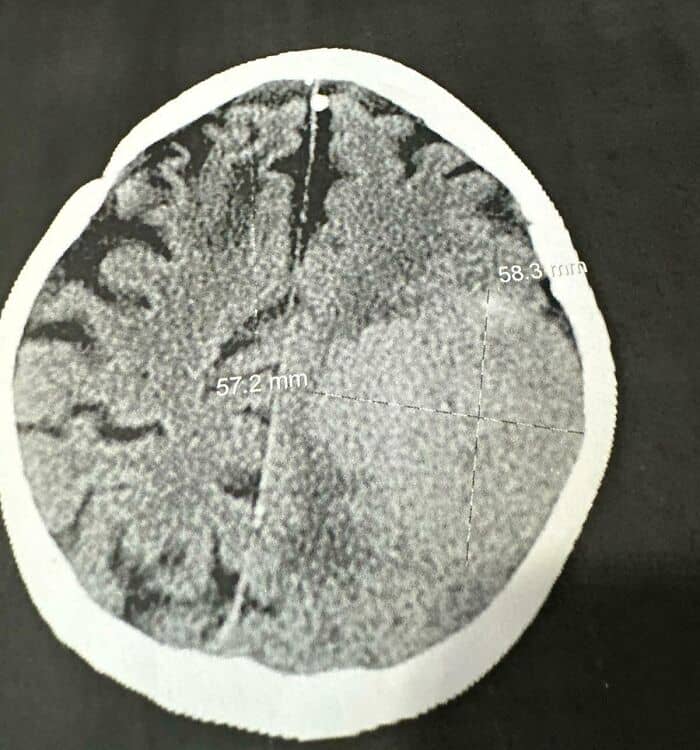

#1 My Aunt Fell At Work. My Aunt Fell At Work On Monday And The Scan She Got To Check For A Concussion Found A 6 Cm X 6 Cm Mass In Her Brain

She had her surgery today and they got it all!